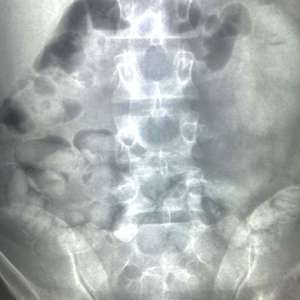

În urma controlului efectuat cu ajutorul unui scaner corporal cu raze X aflat în dotarea Poliției de Frontieră, în interiorul abdomenului inculpatului au fost observate mai multe formațiuni neobișnuite, care nu corespund anatomiei umane. În consecință, inculpatul a fost condus la o unitate spitalicească, unde, pe parcursul internării, a eliminat un număr de 62 de cașete, ce conțineau aproximativ 350 de grame de substanță pulverulentă (în prezent aflată în curs de expertizare).